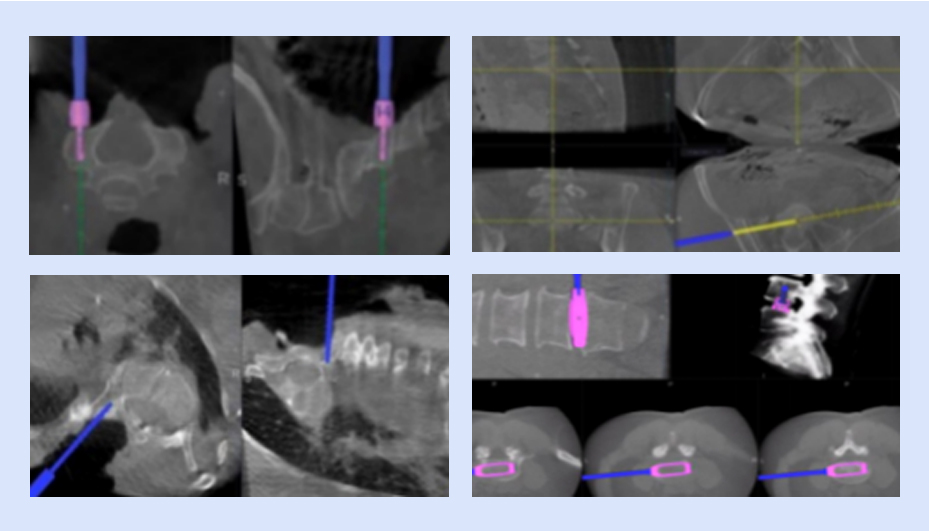

以脊柱療法為中心的可視化賦能

· 從顱到骶全脊柱

· 從開放到微創全術式

· 從脊柱退變、脊柱側彎、骨創傷到骨腫瘤等全病種

全流程可視

可視化置釘

確保導航設備正常運行,檢查定位系統、手術器械、置釘系統等是否完好,以及設備是否處于最佳工作狀態

可視化椎間融合

具備全套導航專用椎間融合工具,實現從椎間隙定位、放置通道、椎間處理、試模、放置融合器的全程可視化,提高手術效率,做到精準融合。